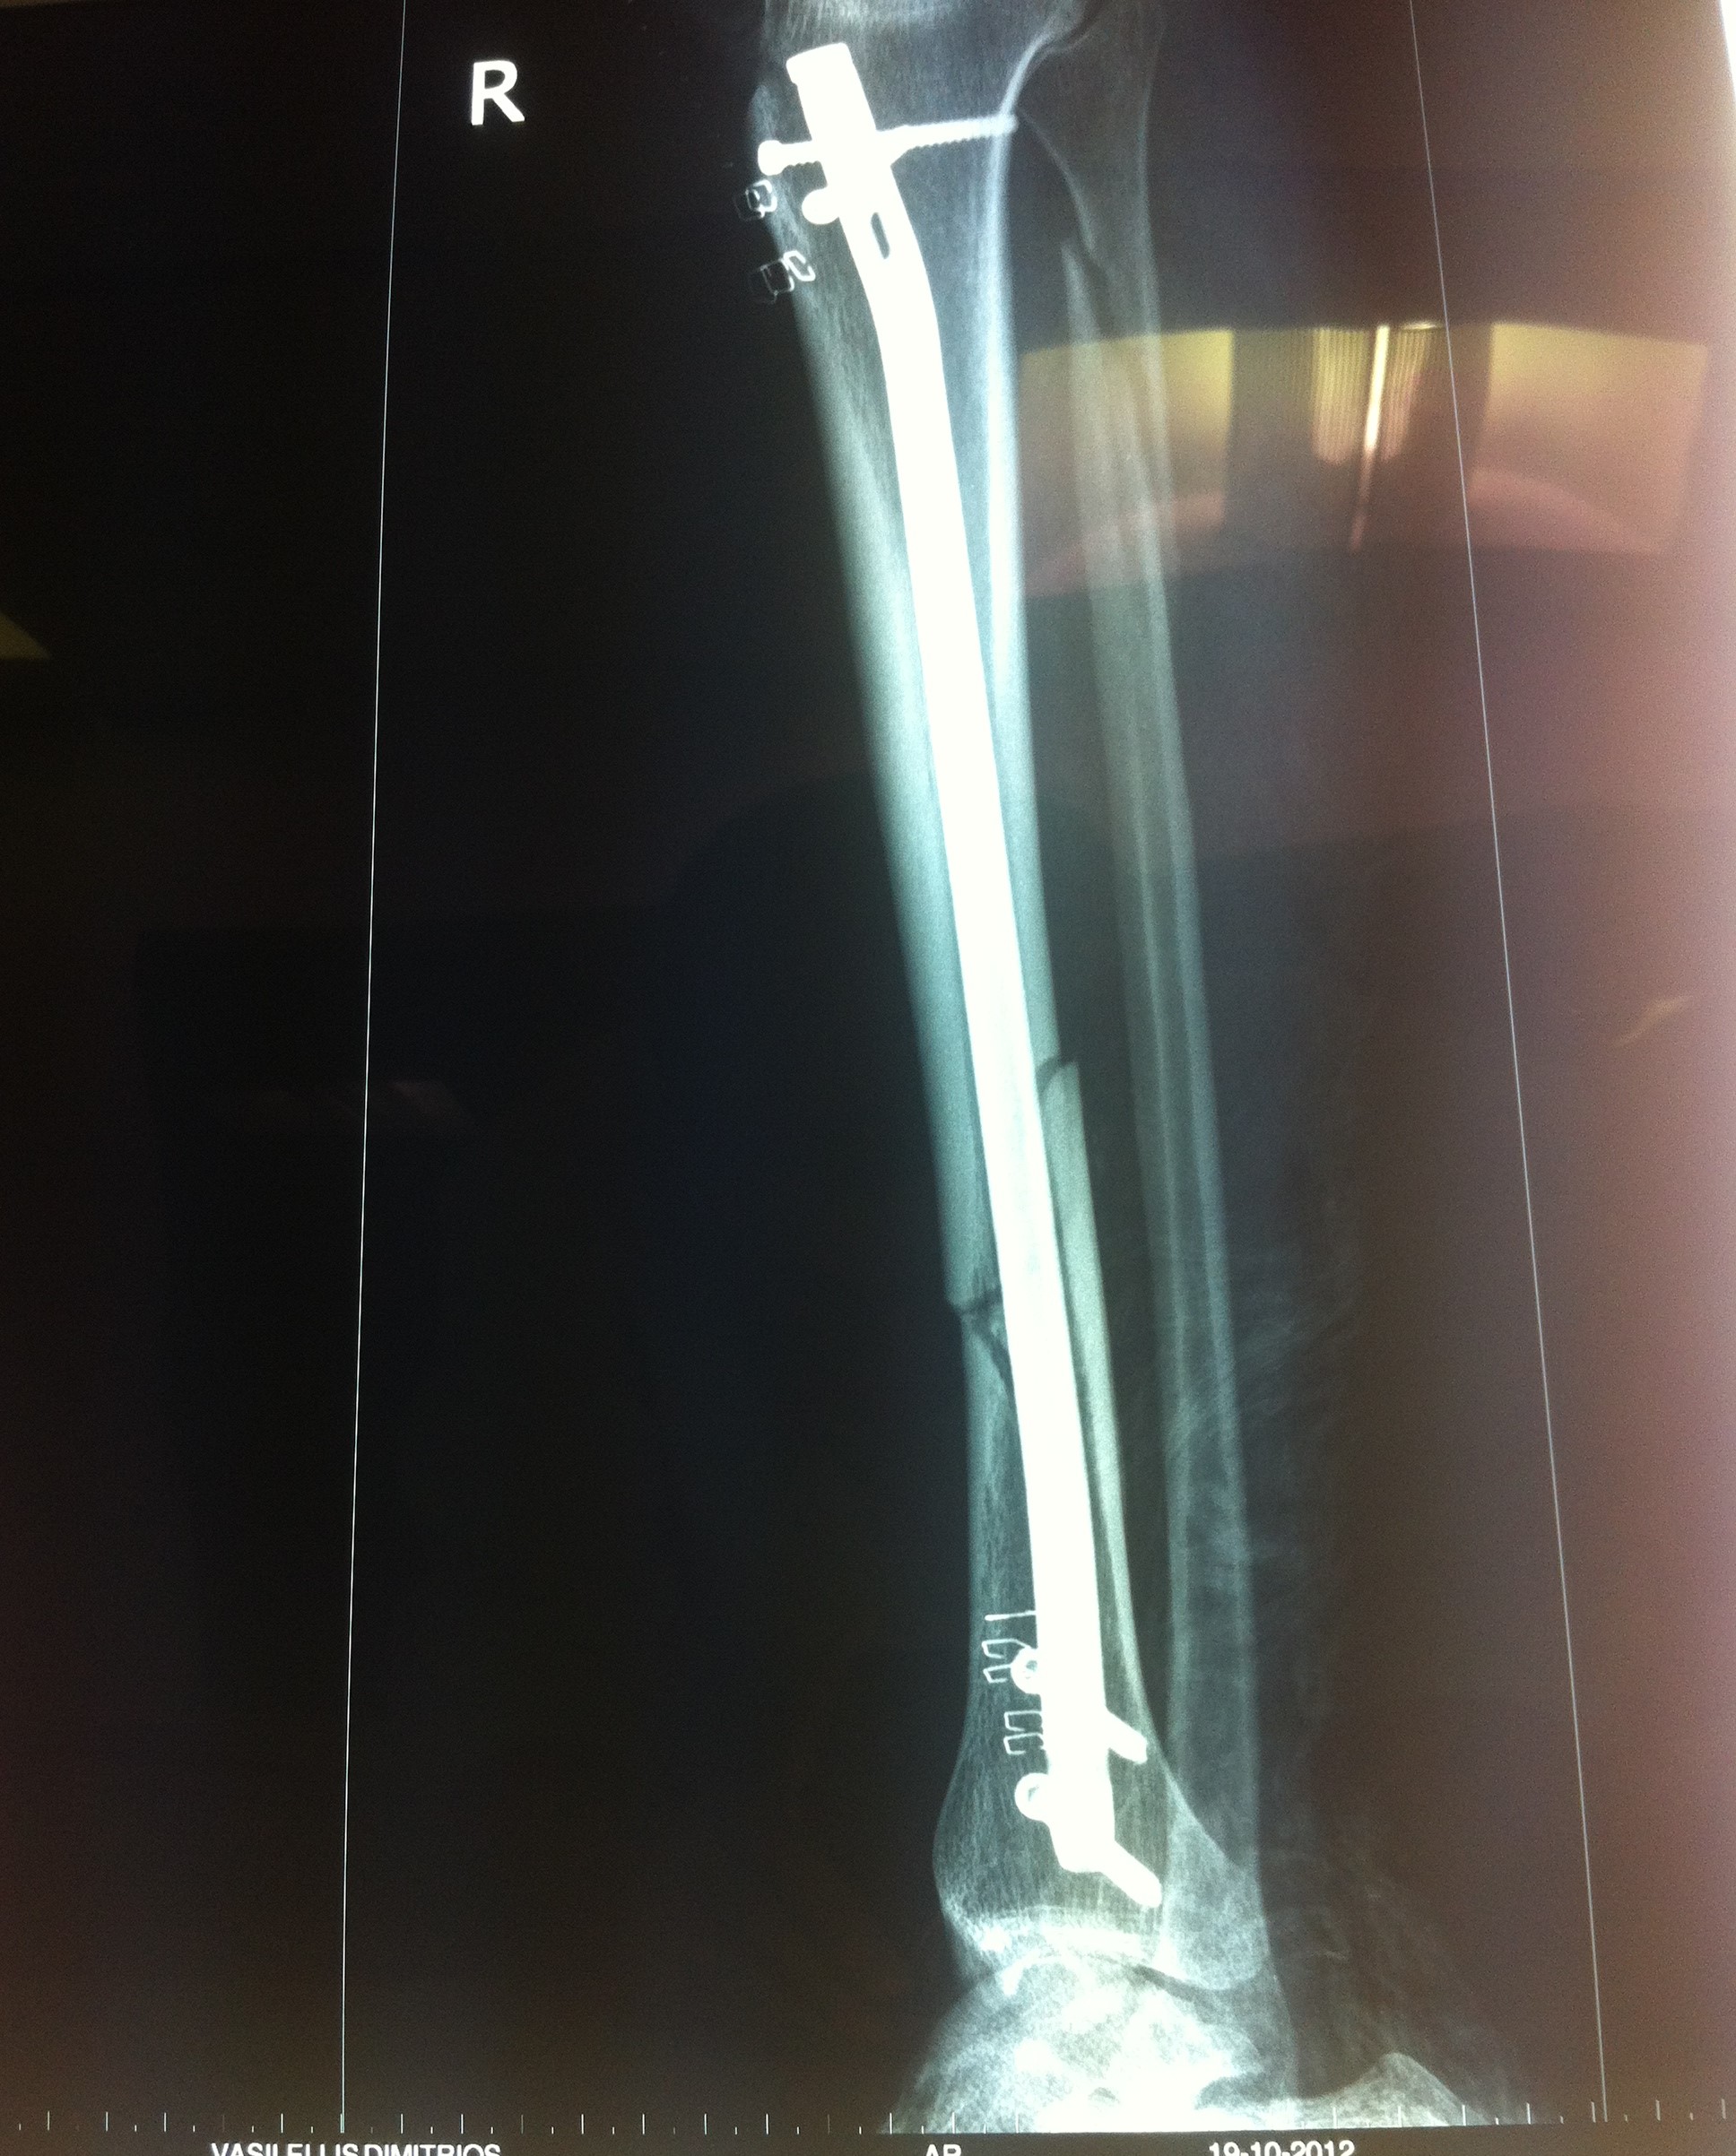

Από την άλλη, η χειρουργική μέθοδος που θα επιλεχθεί εξαρτάται από τον τύπο του κατάγματος, τις λοιπές συνοδές κακώσεις και την εμπειρία του χειρουργού. Ένα κάταγμα κνήμης μπορεί να αποκατασταθεί με τοποθέτηση ενδομυελικού ήλου, με ανοικτή ανάταξη και εσωτερική οστεοσύνθεση με πλάκες και βίδες ή με εξωτερική οστεοσύνθεση.